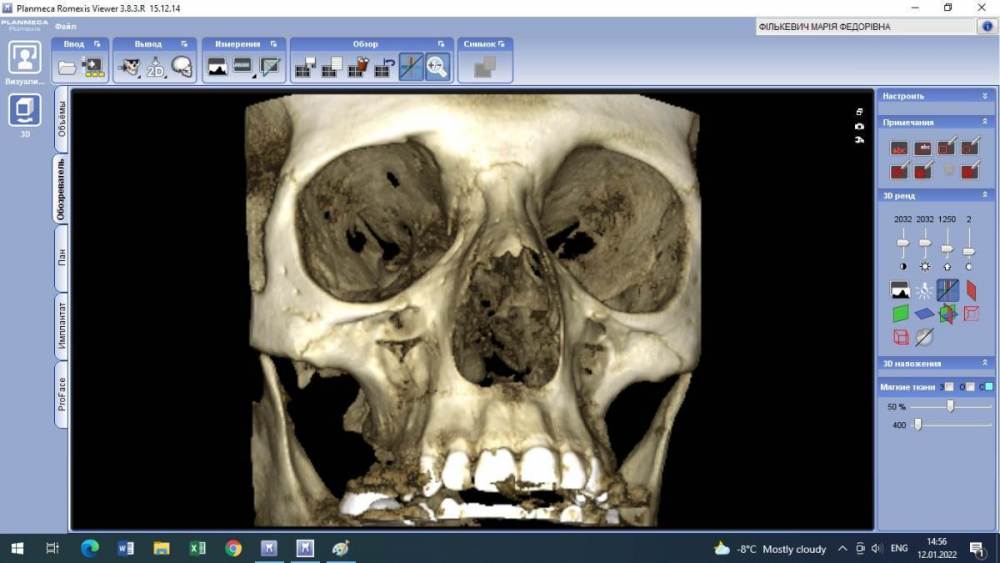

Lyubanya Опубликовано 12 января, 2022 Поделиться Опубликовано 12 января, 2022 Здравствуйте, коллеги. Вот такой случай. 11 зуб, пациентка 1963 г.р. Найдено случайно на КТ, делала его 3.09.21 по другому поводу, я взяла посмотреть для эндо премоляров. Визуально во рту вижу легкую розоватость пришеечно, и есть место, где цепляет зонд. Вопросов много. Каков точный диагноз? И что делать с этим зубом? Есть ли у него шансы пожить еще? Я так понимаю по возможности делается эндо в таком зубе. Если есть шансы то какова тактика? Ссылка на комментарий

Дмитрий Л. Опубликовано 15 января, 2022 Поделиться Опубликовано 15 января, 2022 Это инвазивная цервикальная резорбция, связи с пульпой нету, хирургически можно откинуть лоскут и реставрировать. Риск рецессии. Другое лечение - выжидание, риски прогресса с потерей зуба, смотрите на возраст пациента. 1 Ссылка на комментарий

Lyubanya Опубликовано 16 января, 2022 Автор Поделиться Опубликовано 16 января, 2022 8 часов назад, Дмитрий Л. сказал: Это инвазивная цервикальная резорбция, связи с пульпой нету, хирургически можно откинуть лоскут и реставрировать. Риск рецессии. Другое лечение - выжидание, риски прогресса с потерей зуба, смотрите на возраст пациента. А вот размытость дентина вокруг хода канала, это она же? Думала насчет лоскута, но я так понимаю поможет он не особо, там альвеола уже.? Ссылка на комментарий